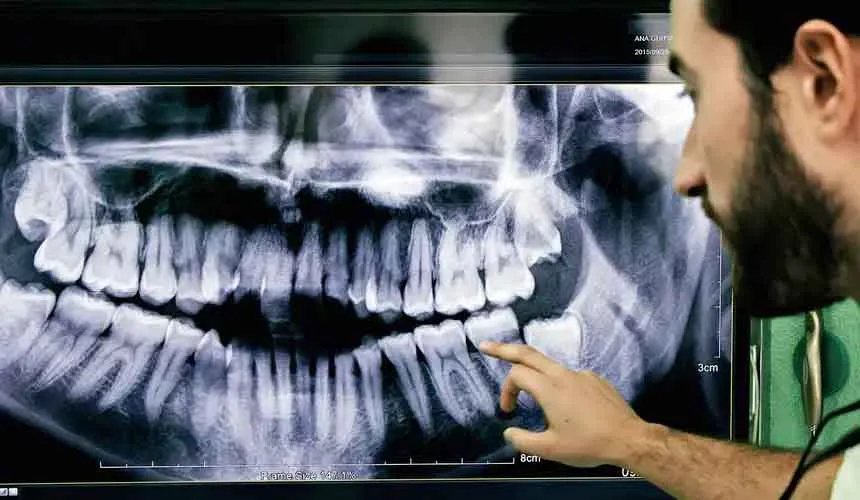

تشخیص میزان پوسیدگی دندان ها فقط با استفاده از عکس OPG امکان پذیر است. اصطلاح رادیوگرافی به مجموعه عکس هایی گفته می شود که با استفاده از اشعه ایکس ثبت می شوند. با این که تفسیر عکس دندان کار دشواری نیست، اما نیاز به دانش و دقت زیادی دارد.

عکس رادیولوژی دندان نقش مهمی در تشخیص و درمان مشکلات دهان و دندان دارد. با کمک این تصاویر، دندانپزشک می تواند پوسیدگی های پنهان، عفونت های ریشه، وضعیت دندان عقل و سایر مشکلات ساختاری را به درستی شناسایی کند. استفاده از دستگاه های رادیوگرافی دندانپزشکی این امکان را فراهم می کند که تصاویر دقیق و باکیفیتی از دندان ها و فک گرفته شود و روند درمان با دقت بیشتری انجام گیرد.

تحلیل و تفسیر عکس دندان OPG دندان یک روش تشخیصی در دندانپزشکی است که در آن با استفاده از تصاویر پیشرفته، به دندانپزشکان کمک می کند تا به طور دقیق تری ساختارهای داخل دهانی را بررسی کنند . در این تکنیک پزشکی از ترکیب تصویربرداری دیجیتال با روش های تحلیل و تفسیر تصاویر استفاده می شود. با استفاده از تفسیر این نوع از عکس ها، نقاط ضعف و مشکلات دندان ها به طور دقیق بررسی و تفصیل می شوند.

این فرآیند که با کمک محاسبات رایانه ای انجام می شود. تا حد زیادی خطاهای احتمالی را برطرف خواهد کرد. بنابراین با تحلیل و تفسیر این نوع از تصاویر، دندانپزشک بهترین روش درمانی را برای بیمار می یابد و با بررسی نقاط قوت و ضعف وضعیت دندان های بیمار، به نتیجه بهتری دست می یابد.

راهنمای خواندن و عکس OPG

تفسیر و خواندن عکس OPG دندان مناسب دندانپزشک ها و افرادی است که علاقه مند به بررسی رادیولوژیکی دهان و دندان هستند. عکس OPG عکسی است که تمام دندان های بالا و پایین بیمار را در بر می گیرد. این نوع عکس اطلاعاتی درباره طول و عرض دندان، وضعیت پارادونتالی، وجود ترک و… به پزشک نشان می دهد. عکس های دندانپزشکی کاربردهای زیادی دارند و برای انجام برخی کارهای درمانی مانند ایمپلنت دیجیتال یا ایمپلنت دندان جلو نیاز هستند.

در تفسیر این عکس، ابتدا پزشک باید تمام اجزای دهان و دندان بیمار را شناسایی کند و بعد از آن وضعیت پارادونتالی دندان ها را بررسی نماید. در مرحله بررسی باید به وجود امتداد ریشه دندان، حفره های موجود در لثه، میزان سیالات موجود در پاکت پارادونتال و وجود دیوار بین دندان ها توجه شود.

با توجه به نتایج به دست آمده از عکس OPG پزشک معالج می تواند بهترین روش های درمان را به بیمار پیشنهاد دهد. به همین دلیل است که خواندن و تفسیر عکس دندان OPG برای یافتن بهترین روش درمان بسیار مهم است. همچنین در کنار عکس OPG، استفاده از ابزارهایی مانند سنسور RVG نیز می تواند به تشخیص های دقیق تر و بررسی جزئیات کمک کند.